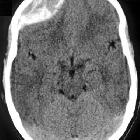

In almost all cases, extradural hematomas are seen on CT scans of the brain. They are typically bi-convex (or lentiform) in shape, and most frequently beneath the squamous part of the temporal bone. EDHs are hyperdense, somewhat heterogeneous, and sharply demarcated. Depending on their size, secondary features of mass effect (e.g. midline shift, subfalcine herniation, uncal herniation) may be present.

When acute bleeding is occurring at the time of CT scanning the non-clotted fresh blood is typically less hyperdense, and a swirl sign may be evident .